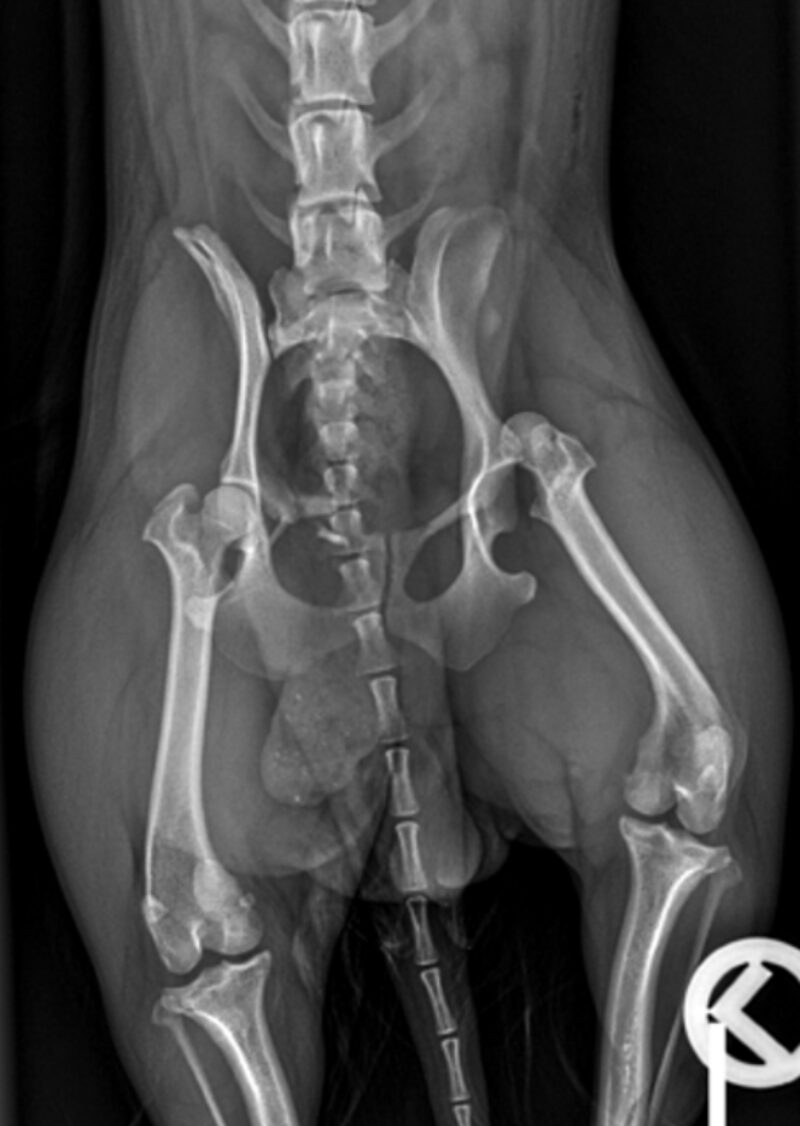

Auf der lateralen und ventrodorsalen Aufnahme des Beckens ist eine segmentale Fraktur des rechten Os pubis erkennbar. Es sind drei Frakturstellen identifizierbar (blaue Pfeile), eine zwischen Corpus ossis pubis und Ramus cranialis, die möglicherweise unvollständig ist. Eine weitere Fraktur im Ramus cranialis ossis pubis und die letzte zwischen Ramus cranialis und Ramus caudalis ossis pubis. Aus dieser Fraktur entstehen zwei Fragmente, von denen eines nahe dem Corpus ossis pubis liegt und geringgradig nach kranial verschoben ist, während das andere frei in den Weichteilen liegt und zwischen den beiden Frakturen zentriert ist. Die Konturen der Frakturen sind alle scharf abgegrenzt, was auf ein akutes Trauma hinweist. Die Symphisis pubis scheint leicht nach links lateral verschoben zu sein. Um eine Verschiebung des Beckens zu ermöglichen, sind drei orthogonale Frakturen erforderlich, die auf diesen Röntgenbildern nicht erkennbar sind.

Der rechte Femurkopf ist vollständig aus dem Acetabulum luxiert und nach kranial und dorsal verschoben (blaue Kreise). Die Weichteile des linken Femurs sind geringgradig verdickt. Im linken lateralen Aspekt der abdominalen Wand ist eine minimale Luftansammlung erkennbar. Beidseits sind die Coxofemoralgelenke geringgradig nach außen rotiert, welches eine laterale Positionierung der Patellae verursacht. Im rechten Kniegelenk befindet sich die Patella jedoch in medialer Position (blauer Pfeilkopf). Es ist unklar, ob ob diese traumatisch oder rasse-bedingt entstanden ist und welcher Grad der Patellaluxation vorliegt. Die sichtbaren caudalen abdominalen Organe sind ohne besonderen Befund.

Es handelt sich um eine akute, geschlossene, monostotische, segmentale Fraktur des rechten Os pubis, eine kraniodorsale Luxation des linken Femurs, eine mediale Luxation der rechten Patella und eine geringgradige Weichteilschwellung des linken Oberschenkels.